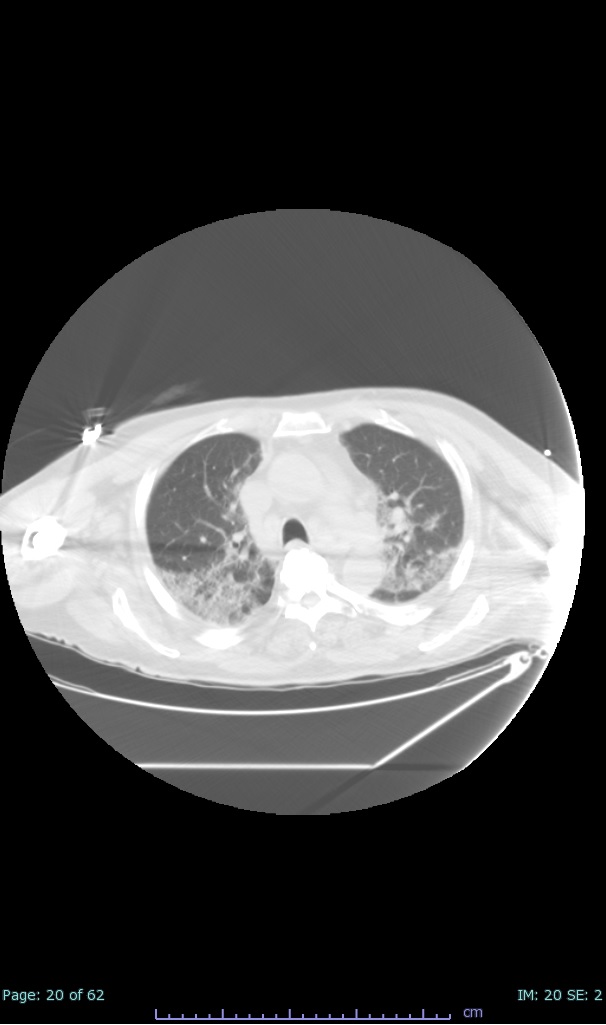

- 100% subpleural involvement, 33% + centrolobular involvement

- 40% even apical/basilar, 27% basilar dom, 5% mid dom. 1/17